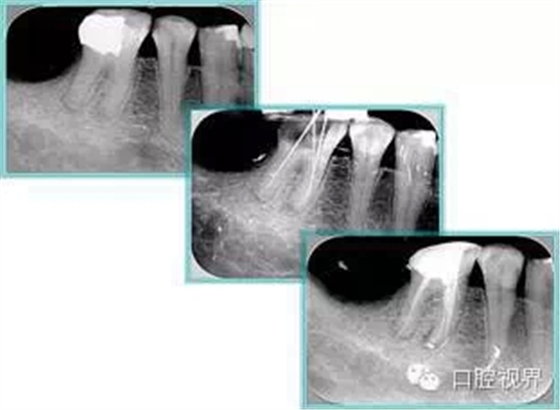

6. 術(shù)后 X 線片

術(shù)后 X 線片用來(lái)評(píng)定根管充填 長(zhǎng)度、致密度(管壁清晰、側(cè)枝)等指標(biāo)。

左圖為根管充填術(shù)后 X 線片。圖中可見(jiàn),根管充填較好。右下圖有白色小點(diǎn),為側(cè)方加壓導(dǎo)致糊劑擠出所致,表明根管充填比較致密。

致密、恰到好處的充填可去除干凈根管里感染灶,機(jī)體逐漸恢復(fù)。

多根牙時(shí)候需進(jìn)行偏移投照,正位投照無(wú)法說(shuō)明具體哪根牙根管充填效果。